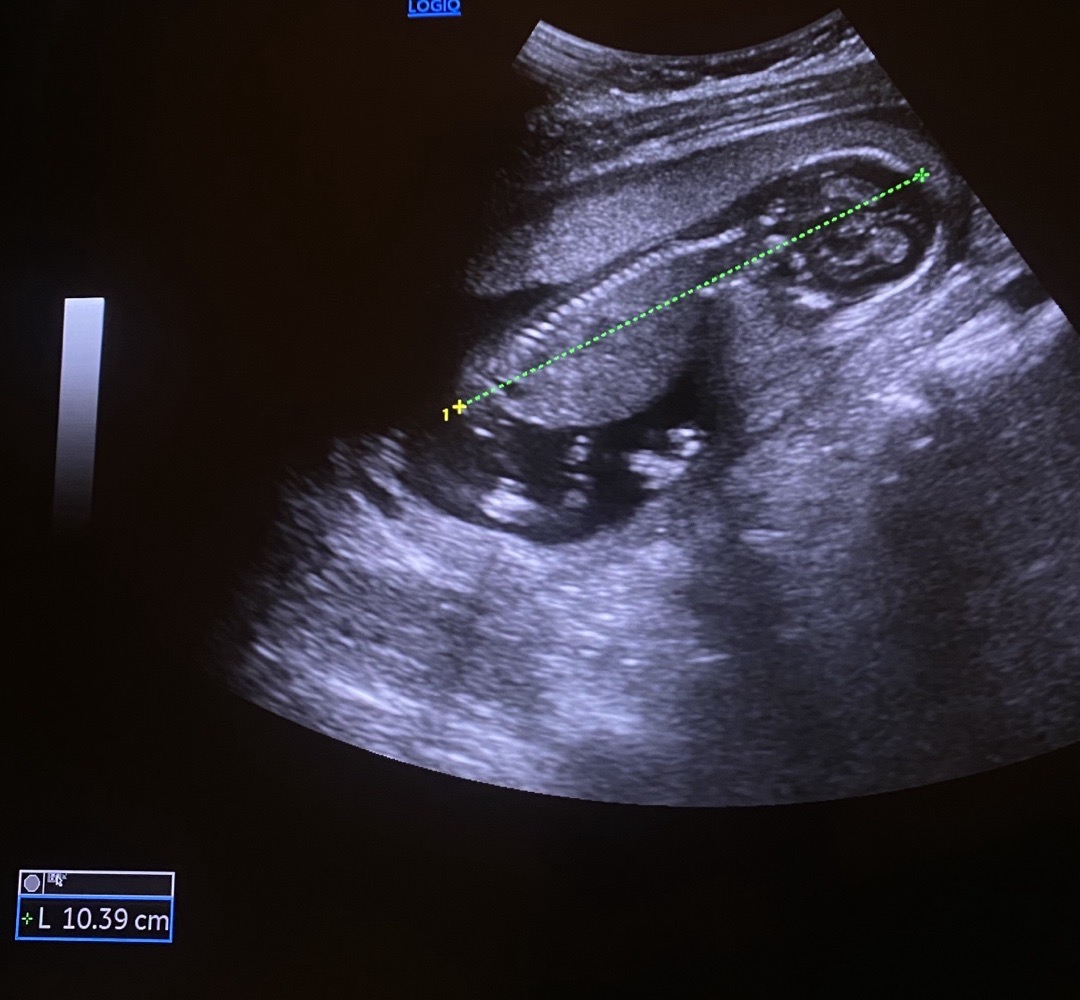

자궁이 작은건지 애기목이 자궁에 껴보여요ㅠ

제가 초음파로 직접본거라 자세히는 모르겟는데 꼭 자궁이작아서 애기목이 자궁에 껴잇는느낌..?이런분들잇나요??

저도 가끔 저렇게 보여요. 의사선생님이 넓은데 놔두고 벽보고 구석에 콕 박혀있는거라고 하셨어요

보는각도마다 다르더라구요 저도 그래서 좁은거 아니냐고 질문드렸더니 바로 다른 각도로 봐주셨어요!ㅎㅎ

저도 16주 초음파 볼때 아기 머리쪽이 좁아 보이더라구요. 점프할때 머리가 자궁에 쿵쿵하고 박는거처럼 보였어요...ㅋㅋㅋ

저도 직접 볼 수 있어서 어제 봤는데 저희 애도 완전 꽉 껴 있더라구요..? 저도 궁금하네요 저희 자궁이 작은건지 원래 다들 그런건지..